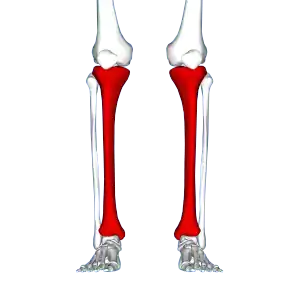

![]() | |

| Red area represents the tibia. Pain is generally in the inner and lower 2/3rds of tibia. | |